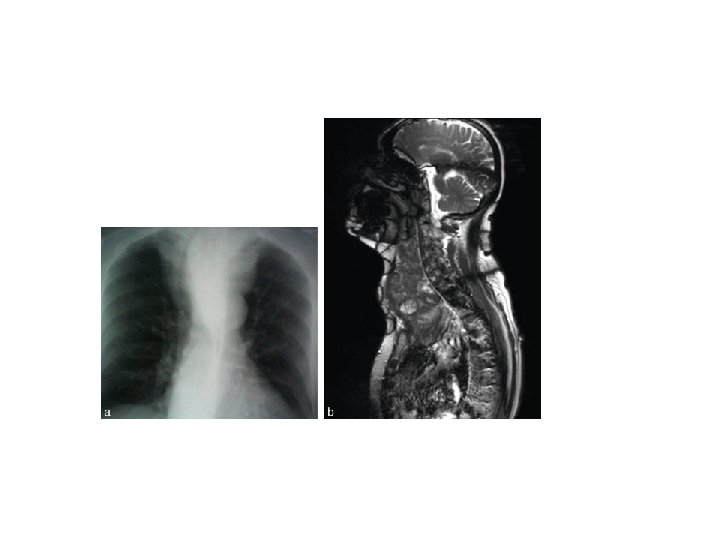

3 - Signes cardiaques : - bradycardie : rythme régulier, lent, inférieur à 60 battements par minute - - assourdissement des bruits du cœur - anomalies ECG : diminution du voltage des complexes QRS, aplatissement de l’onde T ou inversion, augmentation des espaces PR et QT - radologiquement : présence d’un « gros cœur » , en rapport essentiellement avec un épanchement péricardique.

C- Radiographie de la trachée face et profil Compression trachéale par une tumeur de la thyroïde ou Un goitre en montrant une déviation trachéale.